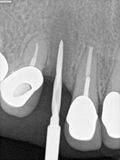

fredlibc | all galleries >> Galleries >> MWang - 13 implant and bone graft > R1.jpg

R1.jpg